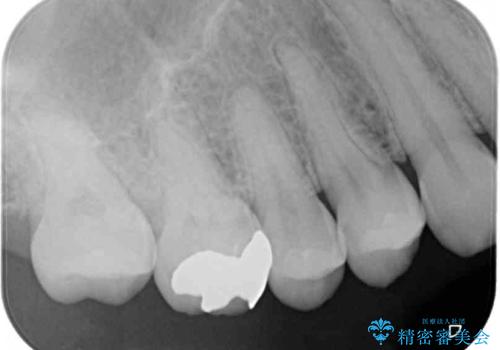

術前の診査では、歯が破折している可能性が高いものの、確実に抜歯が必要と診断ができない状態でした。

状況次第では抜歯が必要となり、その際にはインプラント治療を行うことを了承いただいた上で、破折していない場合には根管治療を行うこととしました。

土台の材料を外して顕微鏡下で確認したところ、歯根にまで及ぶ破折が認められたため、インプラント治療を行うこととしました。